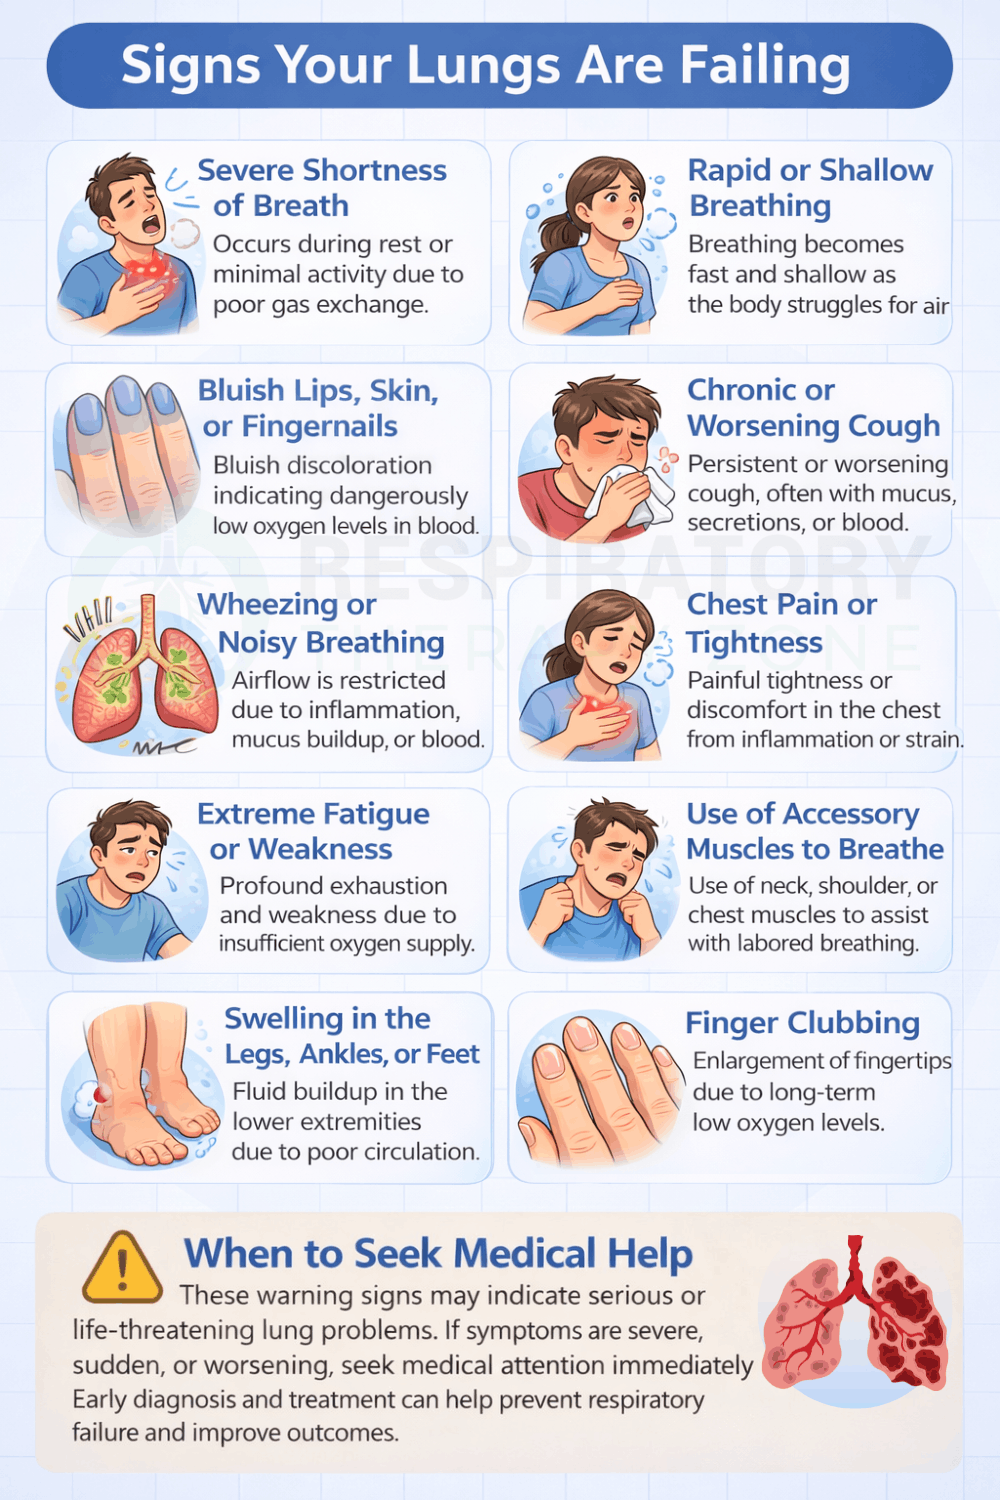

Signs that your lungs may be failing often relate to the body not getting enough oxygen or struggling to remove carbon dioxide. Common warning signs include persistent shortness of breath that worsens with activity or occurs at rest, rapid or shallow breathing, and chronic coughing or wheezing.

Bluish lips, skin, or fingernails can indicate dangerously low oxygen levels, while chest tightness or pain may occur during breathing. Many people also experience extreme fatigue, weakness, or difficulty concentrating due to reduced oxygen delivery to the brain and muscles.

In more advanced cases, visible strain when breathing, swelling in the legs or ankles, or changes in the shape of the fingertips can signal serious and progressive lung dysfunction.

Severe shortness of breath is often one of the earliest and most alarming signs that the lungs are failing. It occurs when the lungs cannot transfer enough oxygen into the bloodstream or remove carbon dioxide effectively.

At first, a person may notice difficulty breathing during physical activity, but as lung function worsens, breathlessness can occur even at rest. Simple tasks such as walking across a room, talking, or lying flat may feel exhausting. Many people describe the sensation as air hunger or feeling like they cannot get a full breath.

Rapid or shallow breathing develops when the body attempts to compensate for impaired lung function. When oxygen levels drop or carbon dioxide levels rise, the brain signals the respiratory system to increase breathing rate. This often results in quick, shallow breaths that are less effective at delivering oxygen to the bloodstream.

While this may temporarily help maintain gas exchange, it can quickly lead to respiratory muscle fatigue and worsening oxygen deprivation. Rapid breathing may also be accompanied by feelings of air hunger, chest tightness, or visible distress. In some cases, breathing may become irregular or labored.

Bluish discoloration of the lips, skin, or fingernails, known as cyanosis, is a serious sign of low oxygen levels in the blood. This occurs when oxygen saturation drops to a level that causes hemoglobin in the blood to change color, giving the skin a blue or gray appearance.

Cyanosis is most noticeable around the lips, fingertips, and nail beds, but it may also appear on the face or extremities. This symptom usually indicates advanced lung dysfunction or severe respiratory distress. It often develops alongside other symptoms such as shortness of breath, confusion, or fatigue.

A chronic or worsening cough can be a warning sign that the lungs are failing, especially when it persists for weeks or produces mucus, blood, or thick secretions. The cough reflex helps clear irritants, infections, and excess mucus from the airways, but when lung disease progresses, coughing may become constant or ineffective.

Conditions such as chronic obstructive pulmonary disease (COPD), pulmonary fibrosis, lung infections, and lung cancer can all cause persistent coughing. Over time, repeated coughing can lead to chest soreness, fatigue, and difficulty sleeping.

Wheezing or noisy breathing occurs when airflow becomes restricted within the airways. This produces a high-pitched whistling sound or rattling noise during inhalation or exhalation. Wheezing is commonly associated with airway inflammation, mucus buildup, or airway narrowing caused by conditions such as asthma, COPD, or severe lung infections.

As lung function declines, wheezing may become louder or more persistent, indicating worsening airway obstruction. Some individuals may also experience chest tightness or difficulty fully emptying their lungs during exhalation.

Chest pain or tightness can occur when lung disease interferes with normal breathing or causes inflammation within the lungs and surrounding tissues. This discomfort may feel sharp, dull, or pressure-like and can worsen during deep breathing, coughing, or physical activity.

In some cases, chest pain may result from infections such as pneumonia, inflammation of the lung lining (pleurisy), or reduced oxygen delivery to the heart. When the lungs fail to provide adequate oxygen, the heart must work harder, which can also contribute to chest discomfort.

Extreme fatigue or weakness is a common symptom when the lungs are failing because the body is not receiving enough oxygen to produce energy efficiently. Oxygen is essential for cellular metabolism, and when levels drop, muscles and organs cannot function properly.

Individuals may notice they tire easily during routine tasks, such as climbing stairs, walking short distances, or performing daily activities. Fatigue may also be accompanied by muscle weakness, reduced endurance, and overall exhaustion.

The use of accessory muscles to breathe occurs when the primary breathing muscles, especially the diaphragm, can no longer meet the body’s respiratory demands. This forces the body to recruit additional muscles in the neck, shoulders, and upper chest to help draw air into the lungs.

Signs include visible tightening of neck muscles, shoulder lifting with each breath, or retractions between the ribs. Some individuals may lean forward while sitting, known as the tripod position, to improve airflow and reduce breathing effort.

Swelling in the legs, ankles, or feet, known as peripheral edema, can develop when chronic lung disease places excessive strain on the heart. When lung function declines, the heart must work harder to pump blood through the lungs, which can lead to right-sided heart failure, also called cor pulmonale.

As the heart weakens, fluid may accumulate in the lower extremities due to poor circulation and increased pressure in the blood vessels. Swelling may worsen throughout the day, especially after prolonged standing or sitting.

Finger clubbing is a physical change in the shape of the fingers and fingernails that can occur with long-term lung disease. It causes the fingertips to become enlarged and rounded, while the nails may curve downward, creating a bulb-like appearance.

Clubbing develops gradually and is often associated with chronic low oxygen levels in the blood. It is commonly seen in conditions such as lung cancer, pulmonary fibrosis, cystic fibrosis, and chronic infections. Although clubbing itself is usually painless, it signals ongoing and significant lung dysfunction.